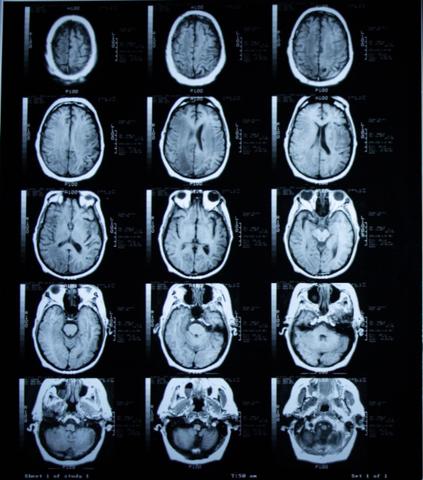

Die Kernspintomographie, auch bekannt als Magnetresonanztomographie (MRT), ist ein medizinisches Verfahren zur detaillierten Darstellung des Körperinneren. Durch die Anwendung von starken Magnetfeldern und Radiowellen werden hochauflösende Bilder erzeugt, ohne dabei schädliche Strahlung zu verwenden. Die Kernspintomographie ermöglicht Ärzten eine genaue Diagnose von Krankheiten und Verletzungen, da sie Gewebe, Organe und sogar das Gehirn präzise abbildet.

Moderne MRT-Geräte eignen sich besonders gut zur Darstellung von Gewebekontrasten wie Muskeln und Sehnen, Gehirngewebe, dem Bauch- und Beckenbereich sowie den Gefäßen. Ein Magnetresonanztomograph ist groß und schwer und sieht aus wie eine Röhre. Allerdings setzen wir an unseren Standorten hochmoderne Kernspintomographen ein, in denen sich Patienten mit Platzangst kaum beengt fühlen.

Die MRT nutzt ein starkes Magnetfeld und Radiowellen, um detaillierte Bilder des Körperinneren zu erzeugen. Moderne MRT-Geräte sind in der Lage, Gewebekontraste wie Muskeln und Sehnen, Gehirngewebe, den Bauch- und Beckenbereich sowie Gefäße präzise darzustellen. Vor der Untersuchung müssen alle Patienten einen Anamnesebogen ausfüllen und einen Aufklärungsbogen unterschreiben. Zudem sollten sie ihren Implantat-Pass, Überweisungsschein, Vorbefunde und eine Medikamentenliste mitbringen.

Die MRT verwendet ein starkes Magnetfeld und Radiowellen, um das Körperinnere bildlich darzustellen. Im Gegensatz zur Computertomographie ist die MRT röntgenstrahlungsfrei und daher schonender für den Patienten. Moderne MRT-Geräte eignen sich besonders gut zur Darstellung von Gewebekontrasten wie Muskeln und Sehnen, Gehirngewebe, Bauch- und Beckenbereich sowie Gefäße.

Die MRT nutzt ein starkes Magnetfeld und Radiowellen, um detaillierte Bilder des Körperinneren zu erzeugen. Diese Bilder ermöglichen es Ärzten, verschiedene Gewebe und Organe genau zu betrachten und mögliche Krankheiten oder Veränderungen zu erkennen. Die MRT eignet sich besonders gut für die Untersuchung der Wirbelsäule, des Gehirns, der Muskeln und Sehnen sowie des Bauch- und Beckenbereichs.

Die Kernspintomographie ermöglicht eine sehr präzise Darstellung des Körperinneren. Durch das starke Magnetfeld und die Radiowellen werden hochauflösende Bilder erzeugt, die detaillierte Informationen über Gewebe, Organe und Gefäße liefern. Dadurch können Krankheiten frühzeitig erkannt und genau lokalisiert werden.

Die MRT eignet sich zur Darstellung verschiedener Körperregionen wie beispielsweise der Wirbelsäule, des Gehirns, des Bauch- und Beckenbereichs sowie der Gefäße. Moderne MRT-Geräte können Gewebekontraste deutlich darstellen, was eine genaue Beurteilung von Muskeln, Sehnen oder Gehirngewebe ermöglicht.